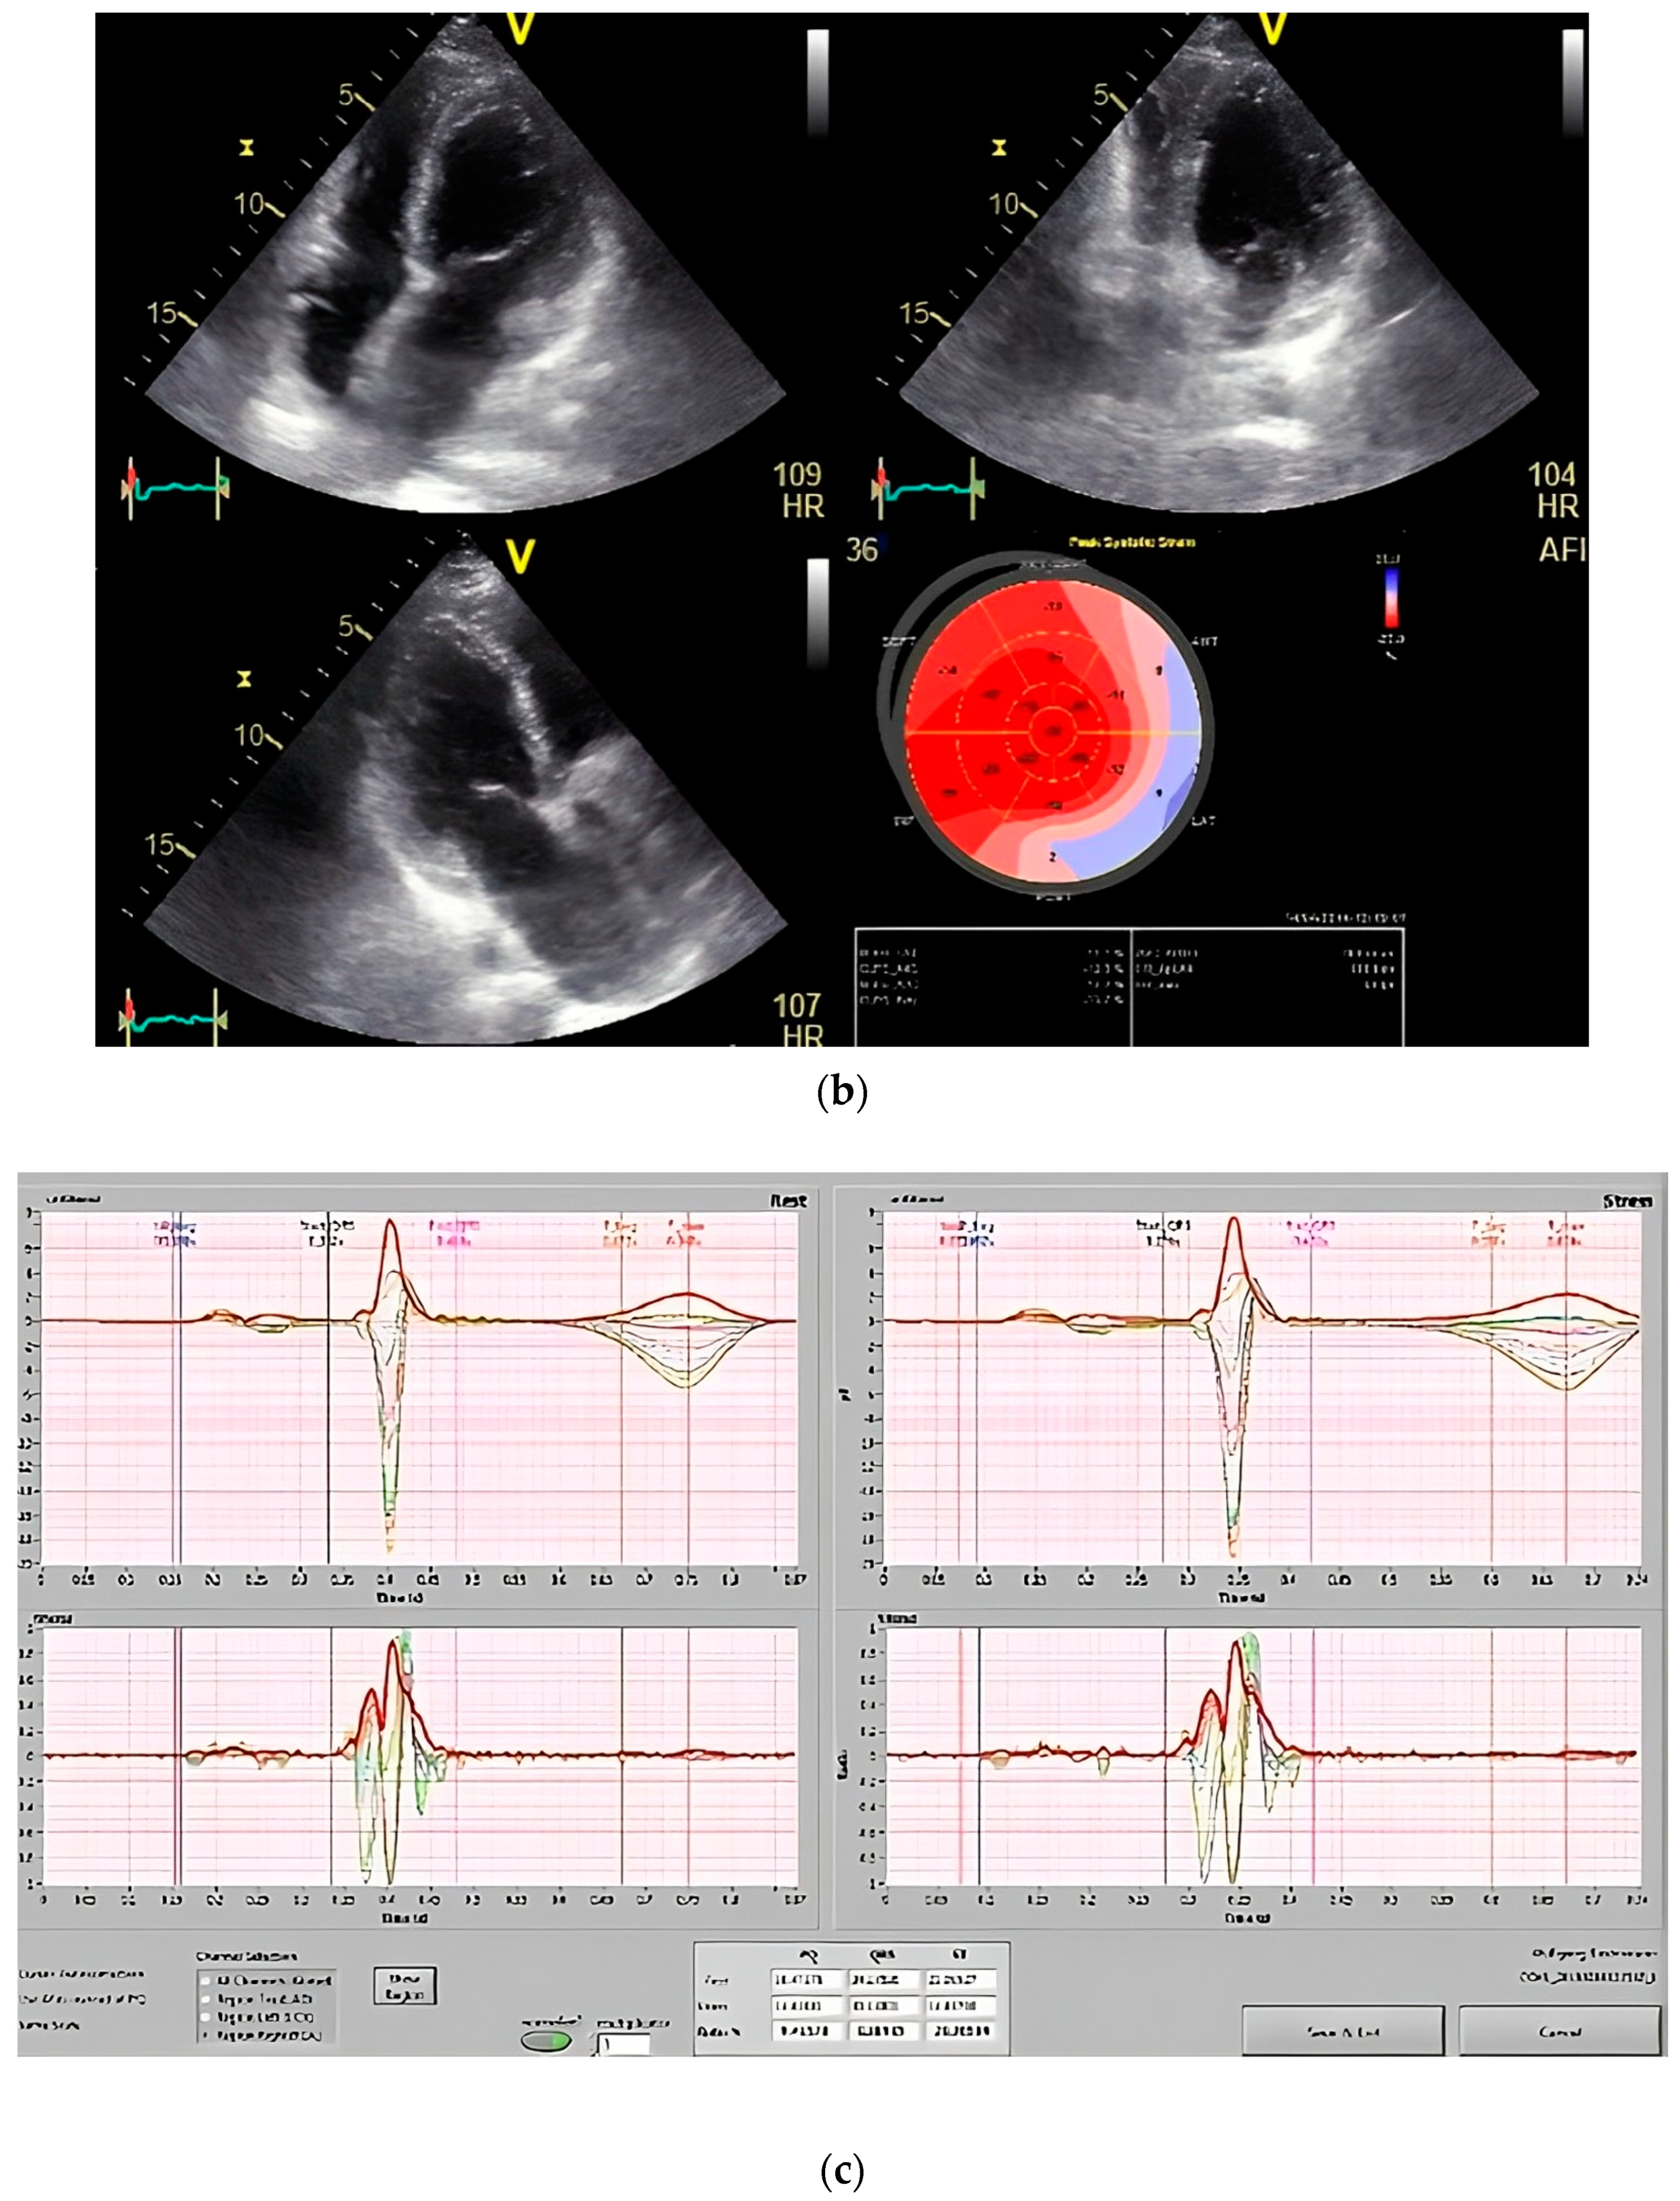

The results of our study revealed a favorable correlation between strain measurements obtained via 2D speckle tracking, both at rest and under stress, and the identification of significant coronary artery disease as confirmed by invasive coronary angiography. The strain parameters exhibited greater sensitivity and specificity during stress testing in comparison to resting states. Importantly, the ST fluctuation rate measured through magnetocardiography showed the highest level of sensitivity (Figure 5).

Figure 5.

(a) Global longitudinal strain (GLS) by speckle tracking at rest showing decreased strain in septal region. (b) GLS by speckle tracking under stress (first phase stress at 20 mg/kg/min intravenous infusion of dobutamine) of the same patient showing decreased strain distributed over anterior and anterolateral region (significant left circumflex stenosis was revealed in coronary angiography). (c) Disturbance of T wave dispersion at stress in the same patient.